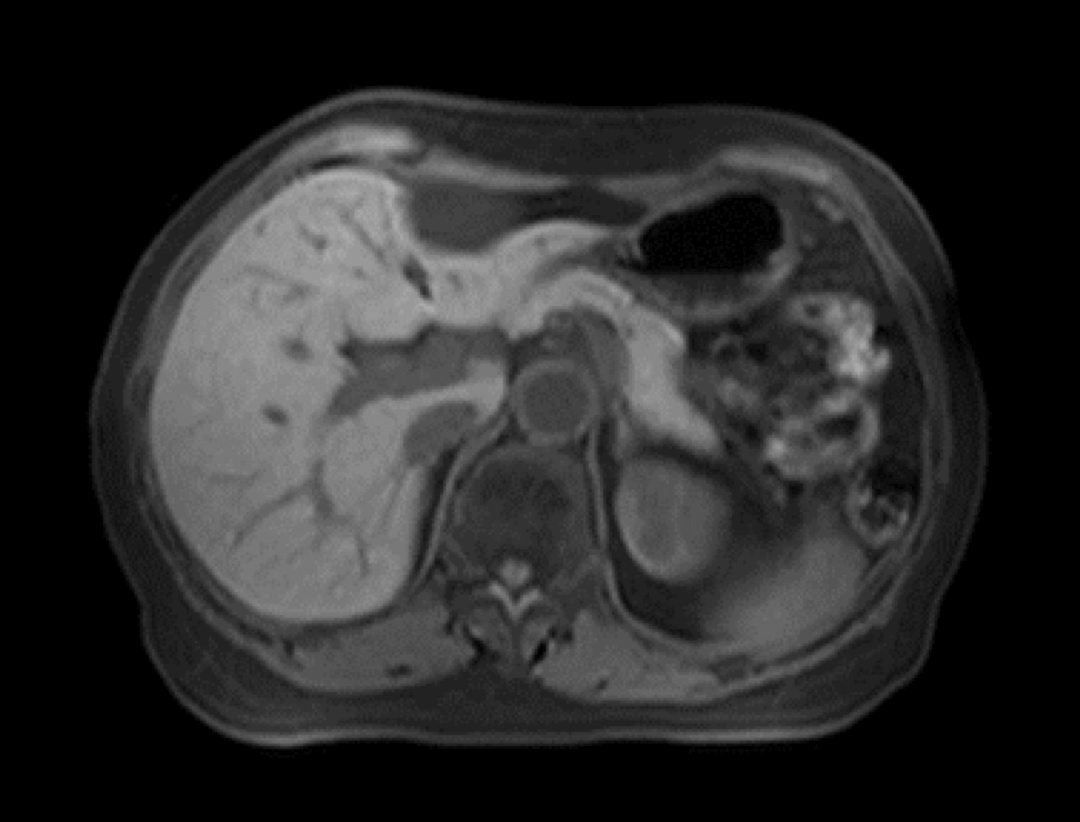

uCS®2.0イメージングをMRI腹部造影ダイナミック撮像に適用することで、16倍の撮影加速度を達成し、組織のダイナミックな信号変化を明確にとらえることが可能です。